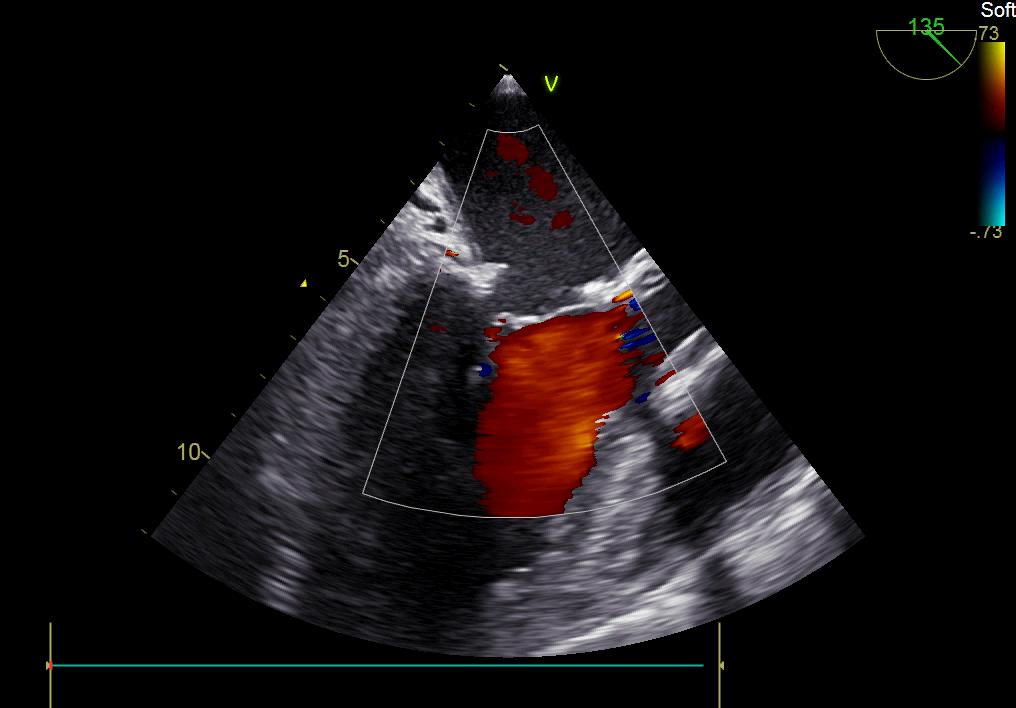

患者何某,42歲男性,因心功能不全入住我院心胸外科,心臟彩超提示二尖瓣后葉脫垂伴有重度返流及心臟擴大,在迅速糾正心衰后,手術便提上日程,心胸外科廖金文主任多次組織全科及兄弟科室討論,在二尖瓣置換及成形術上,最終決定采取二尖瓣成形術。為保證手術安全,討論圍手術期各個細節(jié),所謂細節(jié)決定成敗,因為術前的細致全面,加上術中的一絲不茍及術后的精細化管理,患者術后恢復順利,健康出院,復查心臟彩超未見二尖瓣返流。

術后彩超